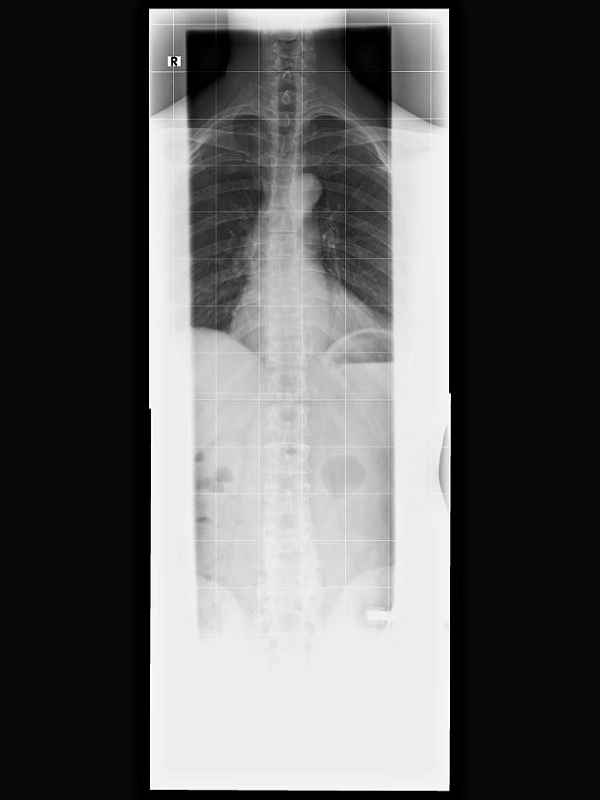

Ich habe mal Röntgenbilder reingestellt.

Aus meiner Sicht würde ich das so beschreiben:

- (doch) kein starkes LWS Kyphose Problem

- die unterste Bandscheibe ist recht stark abgenutzt.

Interessant sind die 'Haken' die am ersten Wirbel wachsen. Hier versucht der Körper auszugleichen, was langfristig zu einer Versteifung an dieser Stelle führen könnte.

Ich habe auch einen Beckenschiefstand oder meine Beine sind unterschiedlich lang, in der Aufregung weiß ich es nicht mehr genau. Der Beinlängenausgleich (rechts höher stehen als links) brachte aber keine bessere Stabilität für die Wirbelsäule. Ich sollte nach Dr. Hoffmann also keine unterschiedlich hohen Schuhe tragen.

Interessant war auch, dass meine Hüftgelenke nicht richtig in der Pfanne sitzen. Normal ist 120 Grad, ich habe aber 160 (der rote Pfeil im 1. Bild: ganz verstanden habe ich das nicht, ob von hinten oder von der Seite gesehen? Muss ich nochmal nachlesen bzw. ne Quelle finden). 160 Grad haben Säuglinge. Da habe ich mich also als Kind auch nicht normal entwickelt. Dr. Hoffmann meinte, dass man das auch korrigieren könnte. Im Moment aber nicht notwendig, da ich keine Probleme mit Hüfte oder Leisten habe.